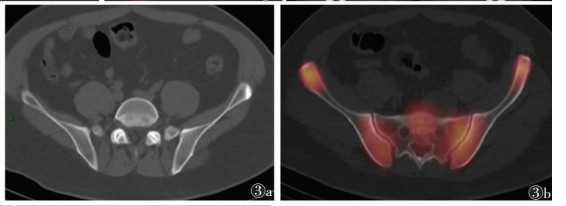

2 结果49例共91处疼痛部位,发生于颅骨颈椎(图 1)、肋骨、髋关节(图 2)、骶髂关节(图 3)、胸椎(图 4)等处的疼痛较剧烈且为持续性疼痛,夜间更明显,并随时间推移逐渐加重,常规非甾体药物缓解不明显。SPECT/CT融合断层显像示阳性40处,其中真阳性35处,假阳性5处;阴性51处,其中真阴性49处,假阴性2处。SPECT/CT融合断层显像对肿瘤疼痛骨转移瘤诊断的敏感度为94.6%(35/37)、特异度为90.7%(49/54)、准确率为92.3%(84/91)。后经病理及临床随访证实5处假阳性病灶中3处为退行性病变,由于存在隐匿性骨质破坏导致骨代谢增高,核素浓聚;余2处,1处为髓腔炎症所致,1处为原发骨肿瘤。2处假阴性病灶由于病灶体积较小,1处位于胸椎重叠部位,1处示溶骨性改变,最后融合显像显示放射性浓聚不明显而导致漏诊。

| 图 3 男,37岁,黏液脂肪瘤骨转移,骶骨疼痛 图 3a CT平扫示:骶骨可见骨质破坏,L4、L5椎体下关节面均可见M形局限性凹陷,边缘硬化 图 3b SPECT/CT局部融合显像示:骶骨及左侧髂骨病灶均见周围放射性核素不均匀聚集,溶骨性骨质破坏区似可见轻微放射性核素聚集。双侧骶髂关节可见放射性核素浓聚,左侧显著 |